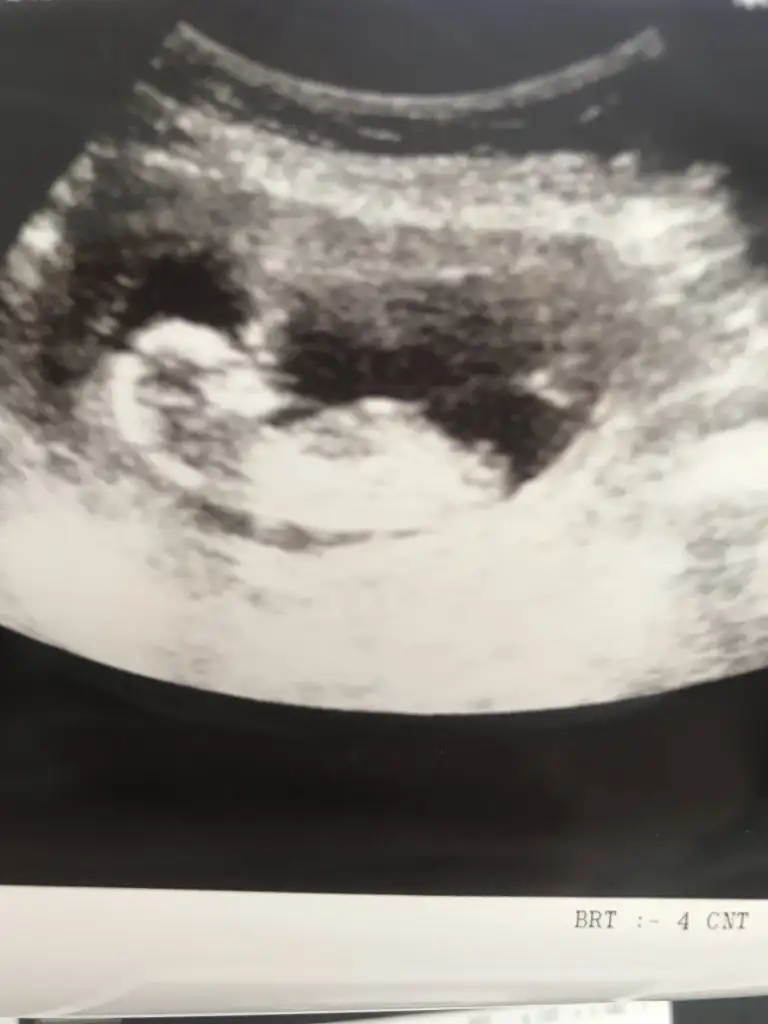

14+3 tahminde bulunurmusunuz🤦‍♂️

• USER_SCOPED_TEMP_DATA_MSGR_PHOTO_FOR_UPLOAD_1619699855146_6793513581238554568.webp

USER_SCOPED_TEMP_DATA_MSGR_PHOTO_FOR_UPLOAD_1619699855146_6793513581238554568.webp

16,7 KB · Görüntüleme: 69